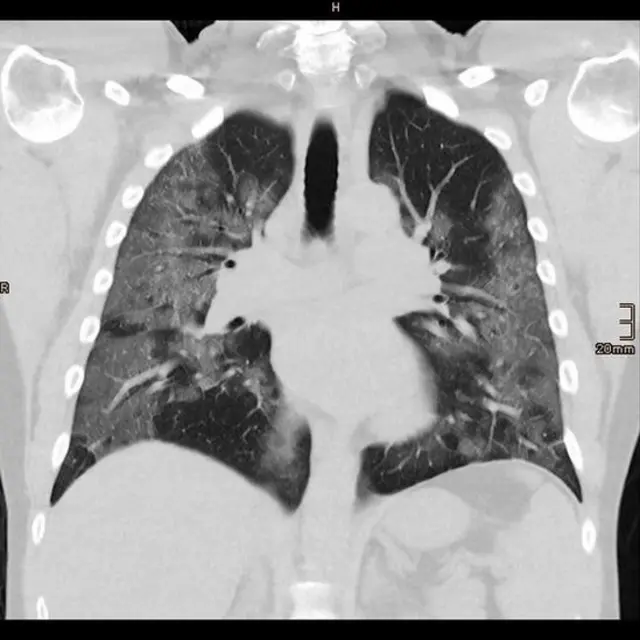

ویروس کرونا میتواند مستقیما انواع زیادی از سلولها را آلوده کند و باعث واکنش ایمنی بیش از حد و آسیب به تمام بدن شود. یک نظر این است که بعد از ابتلا به کرونا، سیستم ایمنی به حالت طبیعی برنمیگردد و این باعث ناسلامتی میشود. این عفونت ممکن است عملکرد اعضای بدن را هم تغییر دهد و اگر به ریه آسیب زده باشد بیشتر مشهود است.